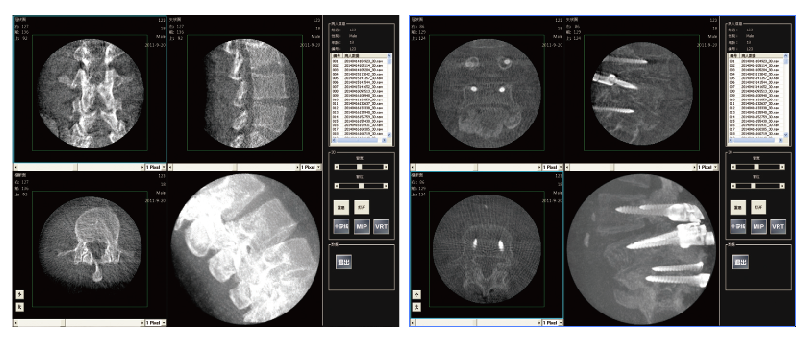

PLX7200三维C形臂骨科手术应用

2、植入物位置更加准确,确保手术安全,提高手术的效果。

3、通过一次多角度自动采集,既可获得全面、准确的影像信息,减少重复采strdfgwgl集次数,投照剂量和手术时间也相应减少。

4、在手术结束之前使用,在手术室既可以完成三维评估,准确地检测定位误差并及时进行修正,不再需要术后移至CT室进行复查,减少因错位等原因进行二次手术的可能。